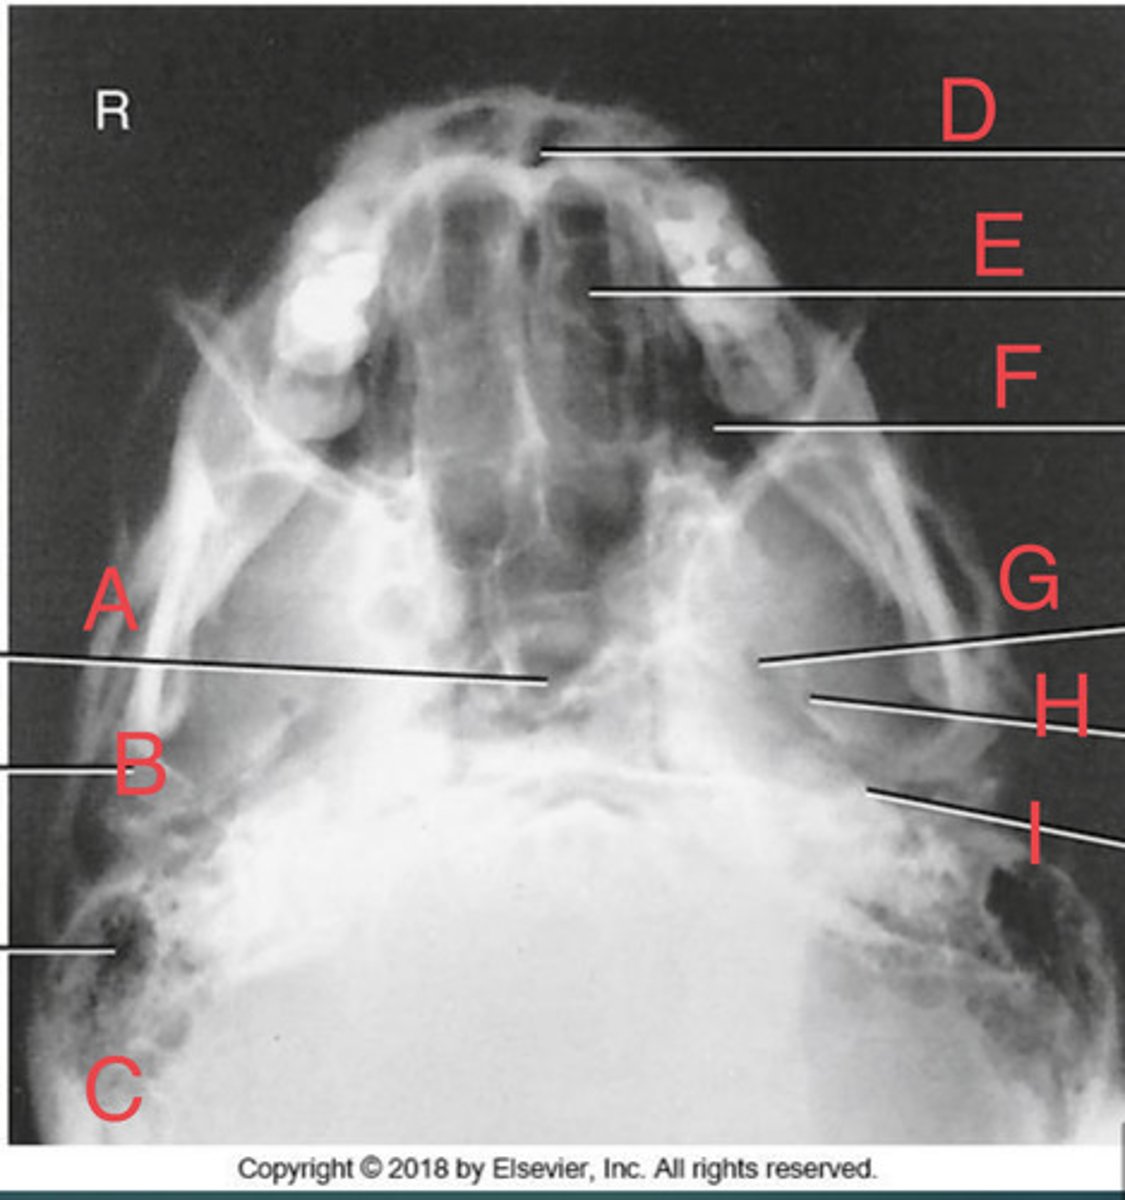

SMV sinuses

What position?

Sphenoid sinus of sphenoid bone

A.

R mandibular condyle of mandible

B.

R Mastoid air cells of temporal bone

C.

Nasal fossa

D.

L. Ethmoid sinus of ethmoid bone

E.

L maxillary sinus of maxilla

F.

L foramen ovale of sphenoid bone

G.

foramen spinosum of sphenoid bone

H.